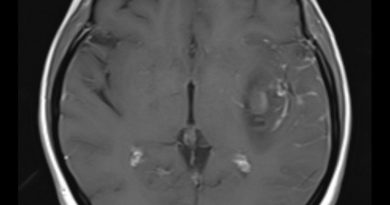

43 yaş, erkek

Nöbet öyküsü

FCD tip 2

Fokal kortikal displazi (Tip II)

Fokal kortikal displazi tip 2 (transmantle sign)